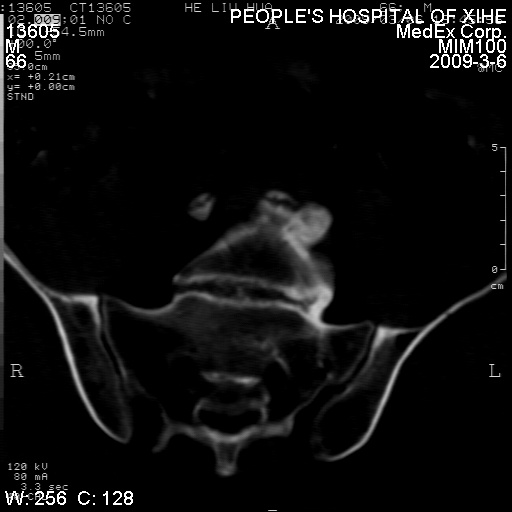

标题: CT18522:男,66岁。考虑结核有错吗 [打印本页]

标题: CT18522:男,66岁。考虑结核有错吗

x线片示:骶骨密度增高。

考虑----腰椎骶化-----退变-----椎管狭窄

退行性变,椎体滑脱

腰椎滑脱并有退变

退行性变,椎体滑脱。建议同椎体平行进一步扫描。